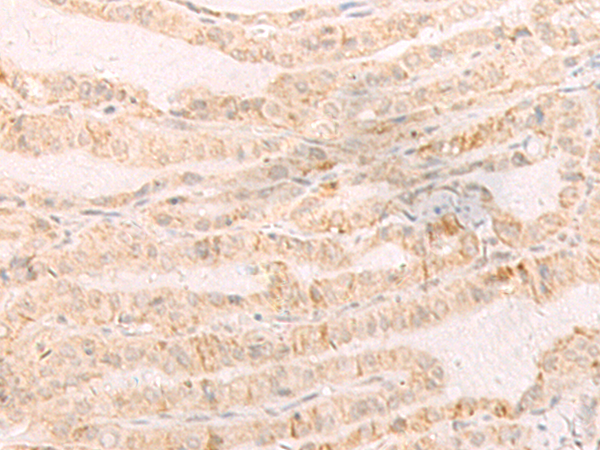

The image is immunohistochemistry of paraffin-embedded Human thyroid cancer tissue using (EREG Antibody) at dilution 1/35.

IHC dilution:1:30-1:150